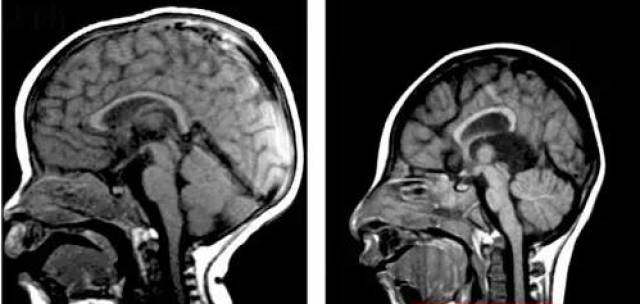

△正常人的头颅(左)和小头症患者的头颅(右)对比,小头症患者的头颅明显小于常人,完全发育后头围也不超过42厘米。